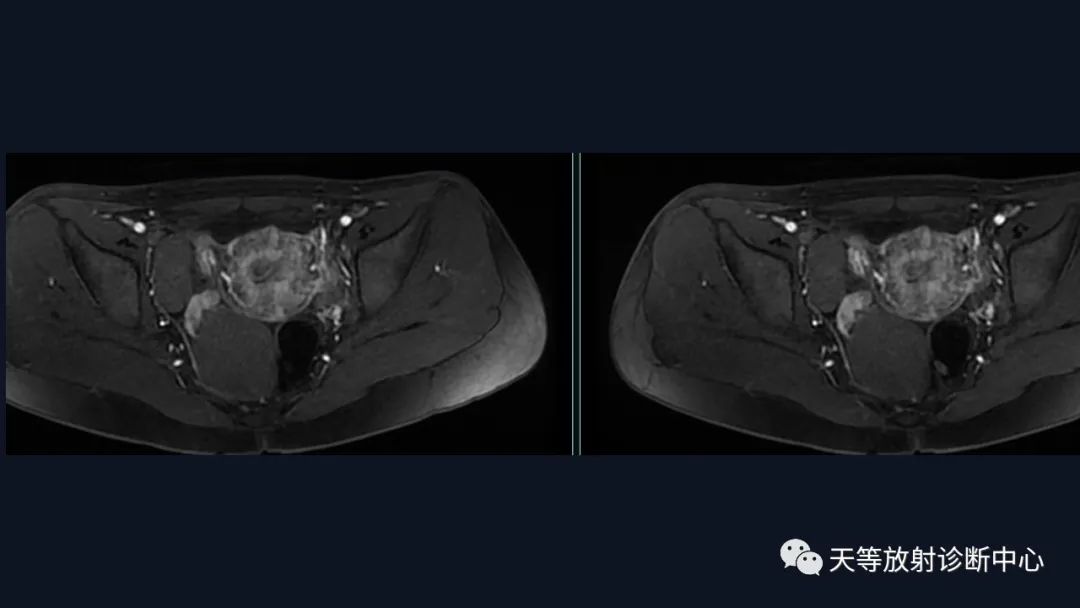

盆腔区右侧附件区见不规侧多发囊性信号肿块影,大小约104mm×37mm×64mm,边界清晰,大囊内信号均匀,相比于肌肉,T1WI呈稍高信号影,T2WI压脂序列呈高信号影,DWI呈高信号,肿块边缘区域尚见多发不同信号结节状囊性信号灶。另外左侧附件区见管状结构及结节状异常信号影,彼此相连,T1WI呈低信号,T2WI稍高信号,DWI呈稍高信号,边界清楚,较大结节直径约30mm。动态增强扫描,右侧囊性肿块见薄壁强化,囊内成分未见强化,而其旁部分结节影明显强化;左侧病灶亦见薄环状强化,但囊壁较对侧病灶厚,囊内成分未见强化,周围边界欠清。

盆腔区右侧附件区见不规侧多发囊性信号肿块影,

边界清晰,大囊内信号均匀,相比于肌肉,T1WI呈稍高信号影,T2WI压脂序列呈高信号影,DWI呈高信号,肿块边缘区域尚见多发不同信号结节状囊性信号灶。

另外左侧附件区见管状结构及结节状异常信号影,彼此相连,T1WI呈低信号,T2WI稍高信号,DWI呈稍高信号,边界清楚,较大结节直径约30mm。

动态增强扫描,右侧囊性肿块见薄壁强化,囊内成分未见强化,而其旁部分结节影明显强化。

最终病例左侧病灶来源输卵管系膜囊肿(副中肾管囊肿)。